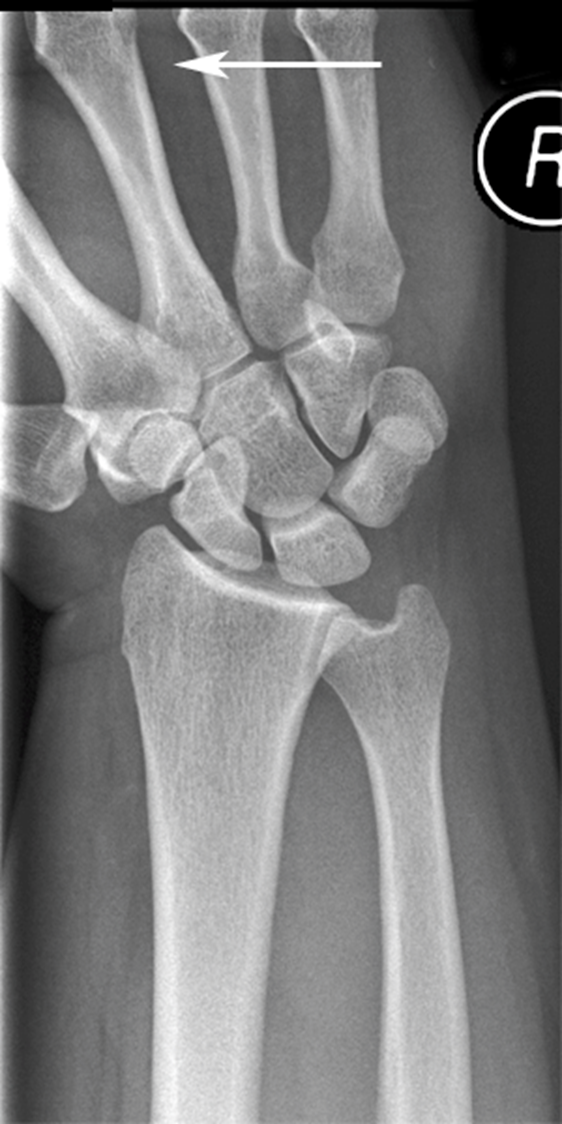

What view is this

ulnar deviation

What does the ulnar deviation best show

scaphoid fractures

scapholunate dislocations